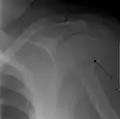

Fracture of the greater tuberosity of the humerus

Multi-fragmented, or comminuted fracture of the proximal humerus with involvement of the greater tuberosity